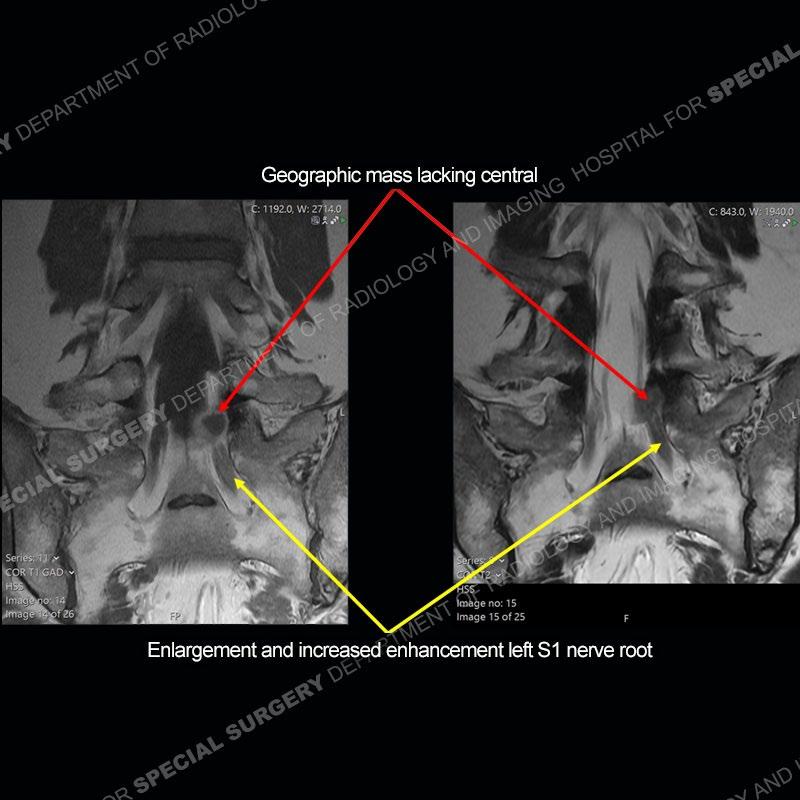

Post operative changes are seen on the left side at L5-S1 where there is near complete removal of the left sided L5 lamina, partial resection of the left L5-S1 facet joint, and resection of the left sided ligamentum flavum. In the anterolateral epidural space about the subarticular recess is a mass that demonstrates similar T1 and T2 signal characteristics to the adjacent degenerated disc. There is enhancement about the periphery of the mass, but the majority of this somewhat geographic or polyploid mass demonstrates no enhancement. The mass exerts prominent mass effect on the left S1 axillary sleeve/proximal nerve root. The left S1 nerve root shows enlargement and increased enhancement as compared to the contralateral right side.

Not as much of a diagnostic dilemma as some other cases but more so just a very nice example of what can be a difficult assessment at times. The evaluation of granulation tissue/scar/epidural fibrosis vs. disc herniation particularly in the earlier post operative period can be very difficult. Clues that can assist in identifying a disc herniation are a more geographic or polypoid nature to the mass, signal characteristics similar to the adjacent degenerated disc, mass effect upon the thecal sac/adjacent neural structures, and a typical enhancement pattern. As the disc material is avascular, as long as imaging is performed in a relatively rapid fashion after contrast administration (within 20-30 minutes), the granulation tissue around the disc will enhance but the disc material itself will not. If there is a marked delay between contrast administration and imaging, there may be diffusion of contrast into the disc making the assessment very difficult. The marked utility of contrast to help delineate disc vs. scar has led to our institution employing contrast fairly uniformly within the first two years following surgery.